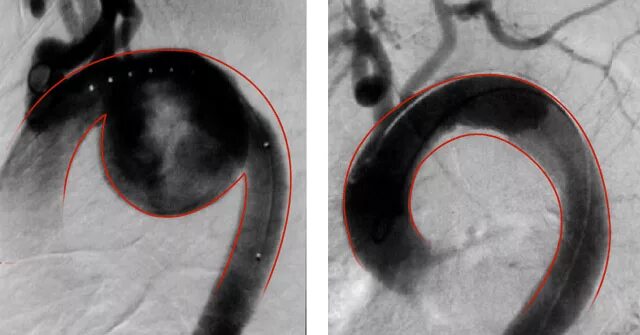

Аневризма аорты инвалидность